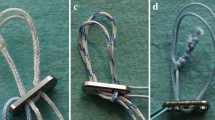

In contrast to previous procedures (Fig. 1), contemporary ACL suture repairs may be augmented with a suture or tape with bony fixation to approximate the ACL remnants, to help to maintain length, allow for early range of motion without compromising the repair site and promote healing [8,9,10, 17, 34] (Figs. 2 and 3).

However, in ‘static’ augmentation, where the suture or tape is fixed to both the tibial and the femoral bone directly, anisometric placement and cyclic loading could lead to elongation of the repair and increase of anterior tibial translation (ATT), and therefore isometric femoral and tibial tunnel position is important [10, 17]. Unfortunately, in practice, isometric tunnel placement can most likely not be achieved (Fig. 2) [17, 20, 40]. ‘Dynamic’ augmentation may address the problems associated with anisometric tunnel placement and cyclic loading by attaching the suture or tape to an additional elastic link (a spring-in-screw mechanism) on the tibial side [17, 34], to allow length changes to occur during knee motion while maintaining reduction of ATT (Fig. 3).

Static tape augmentation of the ruptured ACL

New shuttle wires were placed in the tibial and “isometric” anteromedial femoral tunnels. A cortical button suspension with adjustable loop length (Tightrope™ RT, Arthrex, Naples, Florida, USA) was loaded with a double loop tape (FiberTape™ 2 mm, Arthrex, Naples, Florida, USA), and pulled through the tibial and femoral tunnel with shuttle wires, and it was verified that the button was fixed behind the lateral femoral cortex [12, 39]. The loop of the suspensory fixation was shortened until the tape was pulled approximately 20 mm inside the femoral tunnel. A 3.5-mm bone socket was created 10 mm distal to the tibial tunnel in the anteromedial aspect of the tibia. The socket was tapped to 4.75 mm. The tibial ends of the double loop tape were loaded into the eyelet at the tip of a screwdriver (SwiveLock™, Arthrex, Naples, Florida, USA). The knee was placed in zero degrees of flexion, with a posterior translation force of 80 N imposed on the proximal tibia by the kinematics test rig [25, 34]. While pulling the tape with manual tension in the direction of the tibial tunnel, the tip of the loaded screwdriver was placed in the opening of the tibial socket and the distal ends of the tape were pulled parallel to the screwdriver. The tape was marked at the level of the depth mark on the screwdriver. With the tip of the screwdriver repositioned to the level of the marking on the tape, the SwiveLock™ was pushed inside the 3.5 mm tibial socket manually until the depth mark on the screwdriver lined up with the tibial cortex. The tape was then secured in the tibial socket with the SwiveLock™ PEEK bone anchor interference screw (Fig. 2). The laxity tests were repeated. After the laxity tests, if this procedure was not randomized to be the last procedure, the tape was removed.

Dynamic augmentation of the ruptured ACL

A 2.4 mm guide pin was positioned in the 2.4 mm tibial tunnel. An outside-in tibial socket 30 mm long and 10 mm diameter was reamed over the guide pin with a cannulated drill with depth limitation. A Ligamys™ Monobloc second generation fixation device (Mathys, Betlach, Switzerland) was screwed inside the tibial bone tunnel over the guide pin, until it lined up with the tibial cortex. The guide pin was removed and a shuttle wire was led through the tibial and “isometric” anteromedial femoral tunnels. A Ligamys™ braid was pulled distally through the femoral and tibial tunnels with the shuttle wire, and it was verified that the proximal fixation button abutted the lateral femoral cortex. The knee was placed in 0 degrees of flexion [34]. With the tensioner, the braid was tensioned to maximal manual load and released, after which it was tensioned again to 80-N (Mathys Surgical Instructions) [34]. A clamping cone was fixed into the Ligamys™ Monobloc with a torque screwdriver (Fig. 3). The laxity tests were repeated.